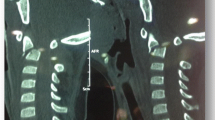

A 6-week-old female Simmental calf was found in lateral recumbency (igloo system, housed with one other calf). The non-ambulatory and recumbent calf was pre-treated by the referring veterinarian with metamizole and then referred to the Clinic for Ruminants for further evaluation. The physical and laboratory examinations (CBC, serum biochemistry profile and blood gases) showed no clinically relevant abnormalities. On neurological examination, the calf appeared conscious and responsive to stimuli but presented in lateral recumbency with non-ambulatory tetraparesis (minimal voluntary movements of all four limbs were preserved). Cranial nerve function was normal. With support, the calf could be raised but showed reduced to absent postural reactions in all limbs. Spinal reflexes were all normal, with increased muscle tone. Conscious pain perception was evaluated to be preserved. Pronounced upper cervical hyperaesthesia with intermittent opisthotonus was evident on neck palpation. Based on neurological findings, the lesion was localised to the C1-C5 spinal cord segments. Based on the clinical history and the calf’s age, the most likely differentials were considered to be trauma, anomaly or inflammation. Lateral cervical digital radiographs (Axiom Luminos dRF, Siemens Healthcare, Erlangen, Germany KV: 69,8, mAS: 25), identified a fractured odontoid process, which appeared to be still attached to the body of the atlas. However, dorsal dislocation of the C2 vertebral body was obvious (Figure 1). The remaining cervical vertebrae displayed no obvious radiographic abnormalities. Based on the radiographic findings our initial diagnosis was a traumatic odontoid process fracture. Instability and spinal cord compression at the fracture site were highly suspected due to the radiographic findings and neurological presentation. Therefore, surgical decompression, anatomical alignment, and stabilisation were favoured for our calf rather than conservative management (such as neck splinting). Potential surgical stabilisation was planned to be performed in collaboration with our small animal neurosurgeons located at the Clinic for Small Animal Surgery and Reproduction. Although the diagnosis of an odontoid process fracture was already established on radiographs, advanced diagnostic imaging was considered to allow better surgical planning and to screen for other traumatic lesions within the remaining cervical vertebrae (because it is reported that multiple vertebral lesions may occur in 5-10% of small animal trauma patients [19,20]). In addition, the owner requested advanced diagnostic imaging examination prior to a cost-consuming surgery to definitively exclude any concurrent and injury-predisposing congenital abnormality at the atlantooccipital region. In the case of a concurrent congenital atlantooccipital fusion, the calf’s owner would have denied any further treatment due to the condition’s potential heritability and associated limitation of future breeding uses. However, because of rapidly deteriorating neurological signs and respiratory distress during trailer transportation to the advanced diagnostic imaging and surgery sites (both located at the Clinic for Small Animal Surgery and Reproduction), the calf was euthanised. MRI and CT examinations were performed immediately post-mortem for scientific reasons. The MRI examination was performed using a 1.5 T magnetic resonance unit (Magnetom Symphony, Siemens Healthcare, Erlangen, Germany). The dead calf was positioned in sternal recumbency because this allowed positioning with only minor neck manipulation (compared with dorsal recumbency) and hence was assumed to lower the risk of artificial and manipulation-induced fracture dislocation; however, dorsal recumbency would have allowed closer contact between the area of interest and the table coils. T1-weighted (T1W; TR: 768, TE: 13), T2-weighted (T2W; TR: 3980, TE: 109) and short tau inversion recovery (STIR; TR: 5790, TE: 61, TI: 140) pulse sequences of the cervical vertebral column were obtained in the sagittal (T1W, T2W and STIR) and dorsal planes (STIR) with a slice thickness of 3 mm (STIR) and 2.5 mm (T1W and T2W). The MRI examination confirmed severe spinal cord compression at the level of the fracture site due to dorsal displacement of the C2 vertebral body and pronounced vertebral step misalignment (Figure 2). Cranial and caudal to the compression site, the spinal cord appeared swollen and exhibited a hyperintense intramedullary signal on the T2W-images and on the STIR-images, with mixed intensity (but predominantly hypointense appearance) on the T1W-images. Based on signal-pattern spinal cord oedema, intramedullary haemorrhage or myelomalacia were considered as potential differentials. A T2* gradient echo (T2*-GRE) sequence would have been helpful to further characterise this spinal cord T2W-hyperintensity but unfortunately was not performed. Dorsal to the compression site, the paravertebral musculature showed a focal area of T2-hyperintensity (with similar appearance on the STIR-images), which was supposed to be indicative of a dorsal traumatic event at this level. A post-mortem CT examination of the cervical vertebral column was performed with a 64-slice, helical CT scanner (Somatom Definition AS, Siemens Healthcare, Erlangen, Germany). Transverse images of the cervical vertebral column were acquired (64 x 0.6-mm detector collimation, 120 KVp, 120 ma, 1 sec rotation time and 512 x 512 reconstructed image matrix). A bone algorithm (B70s convolution Kernel) was used for reconstruction. CT images reflected MRI findings and furthermore identified the fracture site at the synchondrosis between the body of the axis and the odontoid process (Figure 3). The fracture line was directed in a dorsoventral oblique direction from the dorsal area of the odontoid process to the ventral aspect of the body of the axis. Additional findings were bony fragments at the ventral aspect of the fracture line. The degree of odontoid process displacement was calculated to be approximately 40%, employing the following formula used in young children with odontoid process synchondrosis fractures: Distance of maximum displacement of the fractured odontoid process (distance from the cortex of the odontoid to the outer cortex of the body of C2) divided by the anteroposterior diameter (equals the dorsoventral diameter in animals) of the odontoid [21]. Potential congenital malformations predisposing to atlantoaxial instability and other traumatic lesions of the remaining vertebrae were definitely ruled out by advanced diagnostic imaging examination and subsequent necropsy. In summary, this calf was diagnosed with a traumatic odontoid process synchondrosis fracture.

Post-mortem sagittal T2W-image of the cervical vertebral column. The MRI revealed similar findings as the radiographs but displayed pronounced spinal cord involvement. The images reflect displacement of the C2 vertebral body with step misalignment of the vertebral canal and severe spinal cord compression at this level. Next to the compression site, the spinal cord (continuous arrows) shows a T2-hyperintense intramedullary signal. The considered differentials were spinal cord oedema, haemorrhage or myelomalacia. The T2-hyperintense area within the paravertebral musculature located dorsal to the fracture site (broken arrow) is indicative of a traumatic dorsal event. Asterisk = odontoid process.